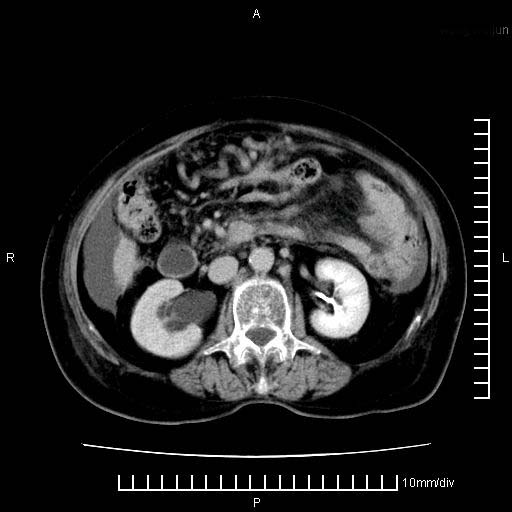

标题: CT28280:腹部增强:女性,80岁

上腹疼痛月余,外院核磁诊断胰腺癌。现临床示右下腹可明显触及包块,可片子上怎么没有看到?

1.胰腺颈体部癌。

2。腹腔积液。

3。右胸腔积液,伴右肺下叶部分萎陷。

4。右肾盂囊肿。

胰腺体部癌累及周围器官,腹膜、粘连

1。胰腺ca伴腹膜腔转移

2。肝左叶低密度灶,考虑转移可能

胰腺体部癌累及周围器官,腹膜、粘连,临床摸到的可能是粘的组织

胰腺结构模糊,胰尾部见囊性包块,周围脂肪密度增高,左肾前筋膜增厚,胸水、腹水。不符合胰腺ca伴腹膜腔转移。考虑胰腺炎伴假性囊肿形成、胸腹腔积液。

右肾盂囊肿。

1)考虑胰腺癌并胰腺假性囊肿形成。2)肝内低密度灶,不排除转移。3)右肾盂积水。4)腹水。5)右侧胸腔积液并右肺下叶部分膨胀不全。

考虑胰腺ca伴腹膜腔转移、肝左叶转移、右肾积水。右胸腔积液。